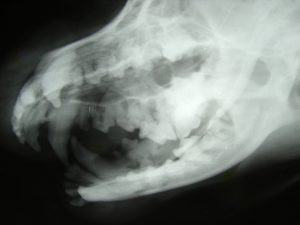

One way we do this is by offering digital dental radiographs. Taking radiographs during dental procedures allows veterinarians to correctly diagnose dental problems. It allows us to look inside your pet’s’ teeth and see their oral cavities. Digital dental radiographs allow us to decide which teeth need to be pulled and which are healthy enough to stay. They also help us decide if owners need to do more for their pets at home.

Digital radiographs are very safe and effective. We will be able to view the radiographs just seconds after they are taken, so they are an invaluable diagnostic tool during dental cleanings.